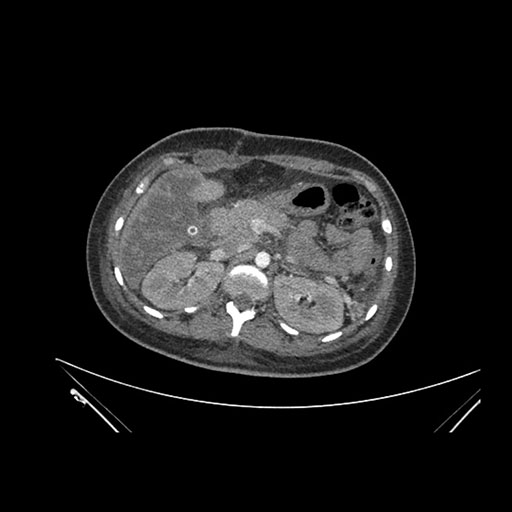

Axial Venous

Imaging analysis

Based on initial findings, which issue(s) would you be most concerned about?